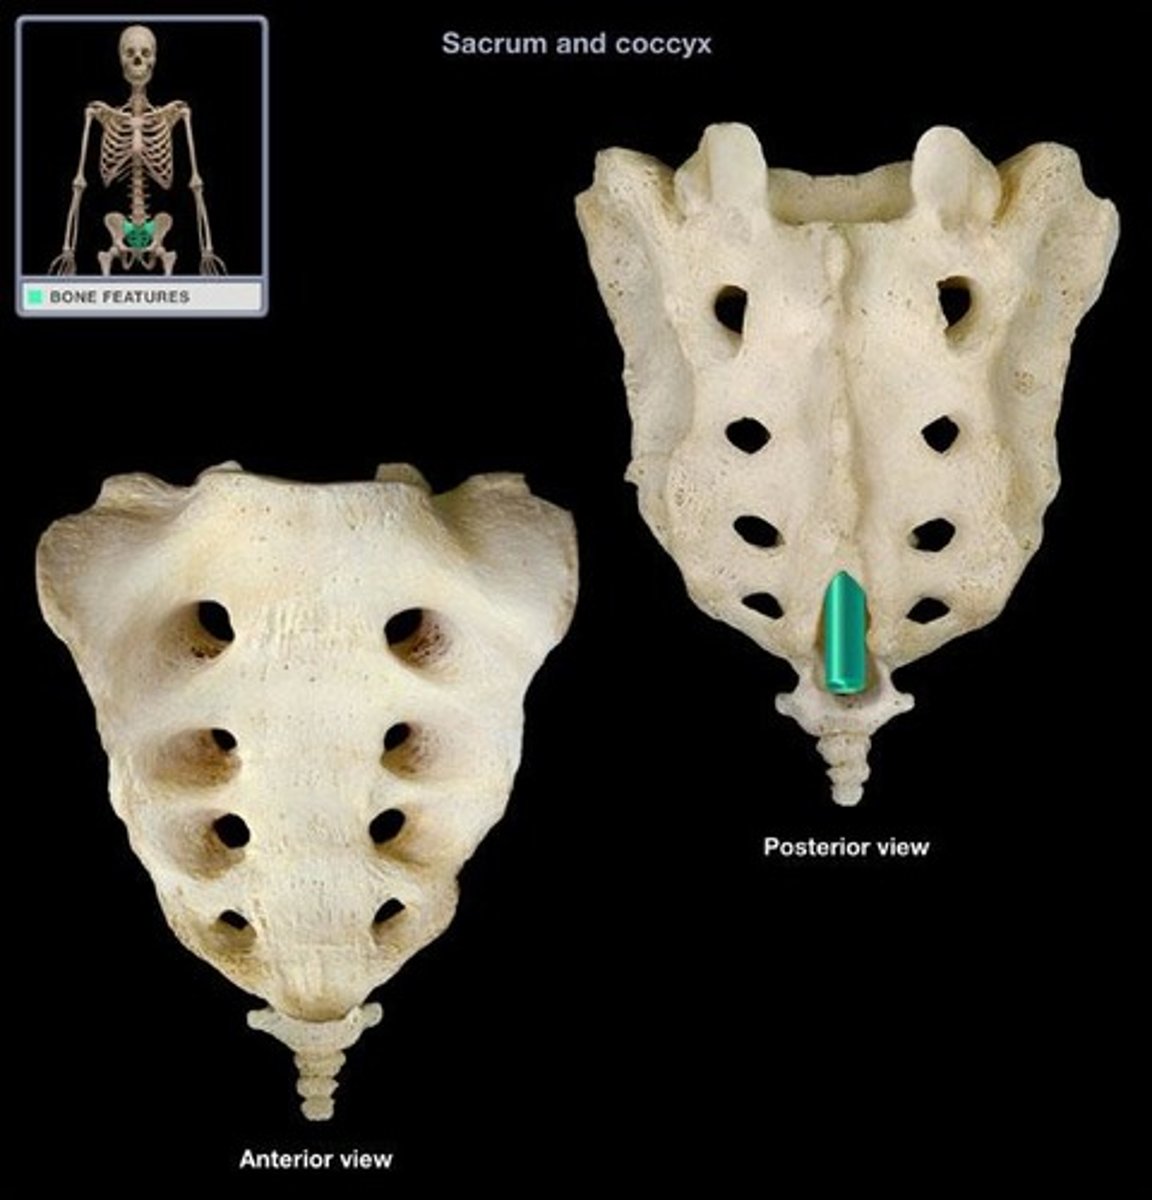

Sacral canal

Sacral hiatus

Sacral foramen/foramina

Median sacral crest